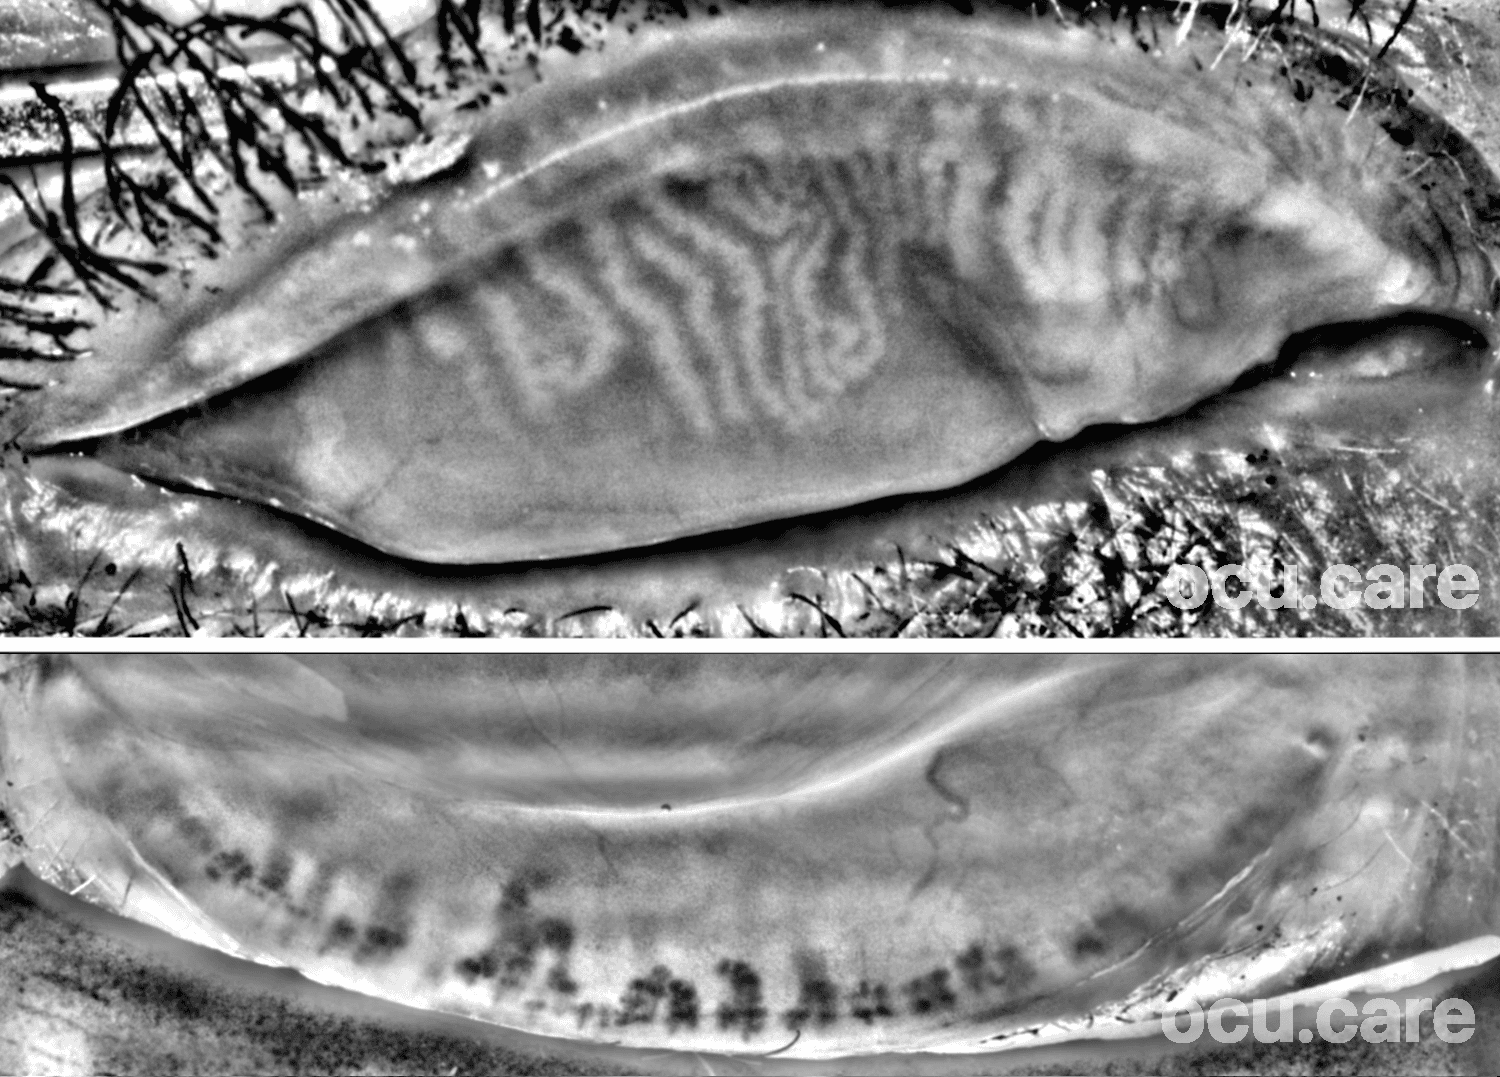

This meibography image was captured in 64-year-old female awaiting cataract surgery (OSDI-6: 4) with the handheld MEA device.

Many patients presenting for cataract surgery have undiagnosed dry eye and meibomian gland dysfunction (MGD). An unstable tear film can distort biometry and corneal topography, increasing the risk of refractive surprises, particularly with toric and multifocal IOLs. Poor tear film quality has been linked to altered measurements, reduced image quality, and lower patient satisfaction, even after technically successful cataract surgery.